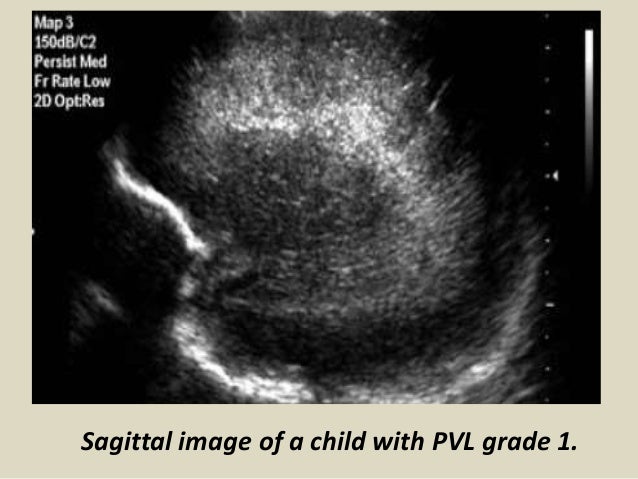

22. 22. Sagittal image of a child with PVL grade 1.

21. 21. Peri Ventricular Leukomalacia (PVL) PVL is also known as Hypoxic-Ischemic Encephalopathy (HIE) of the preterm. It is a white matter disease that affects the periventricular zones. In prematures this white matter zone is a watershed zone between deep and superficial vessels. Until recently ischemia was thought to be the single cause of PVL, but probably other causes (infection, vasculitis) play an additional role. PVL presents as areas of increased periventricular echogenicity. Normally the echogenicity of the periventricular white matter should be less than the echogenicity of the choroid plexus. PVL occurs most commonly in premature infants born at less than 33 weeks gestation (38% PVL) and less than 1500 g birth weight (45% PVL). Detection of PVL is important because a significant percentage of surviving premature infants with PVL develop cerebral palsy, intellectual impairment or visual disturbances. More than 50% of infants with PVL or grade III hemorrhage develop cerebral palsy.